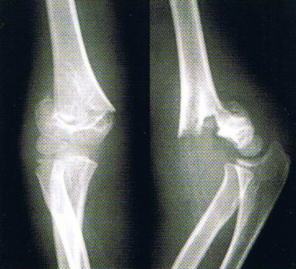

レントゲン写真

肘の部分に激しい痛みと腫れがあり、痛くて肘が動かせないと、この骨折を疑います。骨折片で神経や血管が損傷されると、手や指がしびれて動かせなくなることがあります。レントゲン検査で診断します。